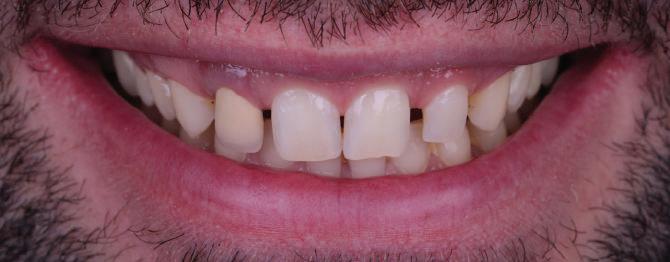

Пациентът постъпи в клиниката с молба за тотална рехабилитация на усмивката. Той не харесваше централ ните си резци, които според него бяха твърде къси и квадратни. Имаше раз стояние от медиално и дистално на латералните му резци. Друго сериоз но оплакване бе свързано с металоке рамичната корона на зъб 12, която бе жълтеникава и неестетична, като цяло не харесваше вида на венците си и както самият той се изразяваше, „вижда се прекалено много от венците при усмивка“.

ЛЕЧЕБНИЯТ ПЛАН ПРИ ТОЗИ СЛУЧАЙ БЕШЕ СЛЕДНИЯТ: Диагностика, фотодокументация,

След диагностиката бяха направени екстра- и интраорални снимки, както и рентгенографии; професионалното почистване бе от изключителна важ ност, бяха дадени и инструкции за лич на орална хигиена. Бе направено интра орално сканиране с Medit i500. Цялата тази информация бе използ вана в приложението Smilecloud за 2D биометричен дизайн. В приложението са налични естест вени форми на зъбите и щом бяха под брани зъби и бе направен дизайн

библиотеката на Exocad. Струва си да се отбележи, че 2D дизайнът от Smile Cloud бе спазен до последния детайл в Exocad smile creator с цел да се създаде 3D obj файл със зъбните форми. След като естетичният дизайн бе готов в model creator модула на Exocad, адитивен 3D мок-ъп модел бе експорти ран и принтиран от принтер Formlabs 3. Моделът бе използван за направата на силиконов водач, за да се изготви мо тивационен мок-ъп в устата на паци ента и да се оценят естетичните па раметри. След като пациентът одобри вида на усмивката си, мок-ъпът бе използван за финализиране дизайна на усмивка та. Мок-ъпът бе използван също така като водач по време на мекотъканна та хирургия, както и при препарация на зъбите.

Препарираните зъби бяха импорти рани в Exocad и насложени върху ес тествените форми от биометричния дизайн, като така стана ясно дали зъ бите са били препарирани коректно. По този начин зъболекарят и зъботехни кът работят в една и съща екосистема и резултатът е оптимален. С короната се справихме чрез диги тална редукция на циркония в Exocad, като по този начин на практика създа дохме циркониево кепе, след което про изведохме фасета от IPS Empress Cad Multi. Кепето от Katana Zirconia на зъб 12 с букално послойно нанесена керами ка бе фрезовано (послойното нанасяне бе направено, за да се подобри връзката и да се осигури адхезивно циментиране на фасетата към циркониевото кепе, както и за да се напасне цветът към този на съседните зъби). При първото сканиране регистрирах ме цялата горна зъбна дъга, така че, ко гато се наложи да сканираме повторно, бе изтрит и сканиран наново само зъб 12, тъй като венците не бяха отдръп нати при второто сканиране.

НА

рентгенографии. Инициална терапия и професионално почистване. Интраорално сканиране с цел диги тално планиране. Регистрация и 3D ориентиране на ок лузалната равнина на горна и долна челюст в пространството. 2D дигитално планиране и дизайн на усмивката посредством приложение то Smile Cloud. 3D дигитално планиране и дизайн на функционалните и естетичните па раметри. 3D дигитален дизайн и адитивен мокъп на горна челюст. 3D принтиране и мок-ъп модели. Мотивационен мок-ъп. Фини корекции за постигане на фи налния дизайн. Мекотъканна хирургия с мок-ъпа като водач Препарация през мок-ъпа, използвай ки дизайна като водач за финалната препарация в Exocad. Циркониево кепе ще бъде циментира но с цел адхезивно залепяне на фасе та на края. Кепето има същия цвят като този на съседните зъби, за да може фасетата да се впише перфект но в цялостната усмивка. Изработване на 12 IPS Empress Cad Multi фасети с послойно нанесена ке ТОТАЛНА РЕХАБИЛИТАЦИЯ НА УСМИВКАТА С ИЗЦЯЛО ДИГИТАЛЕН ПРОТОКОЛ Д-р Калин Маринов и зт. Стефан Петров рамика букално върху зъбните препа рации и върху първичното циркони ево кепе (има възможност за ецване и адхезивно

Една седмица след препарацията на зъбите и циментирането на цирко ниевото кепе бяха изработени 12 IPS Empress Cad Multi фасети. Макро- и микротекстурата на фасе тите бяха направени на ръка, след кое то бяха нанесени 3D характеризации с боички, а полирането отново бе напра вено ръчно, за да им се придаде естест вен и естетичен вид. Предизвикателството тук беше короната да има същите оптични характеристики като тези на остана лите зъби при естествена светлина, през поляризационен и флуоресцентен филтър. 3D принтерът бе Fromlabs, софтуерът за фрезоване – Mill Box, а фрез апаратът –imes icore CORiTEC 350i. В крайна сметка постигнахме ес тествен вид на усмивката с натурал на зъбна морфология при изцяло диги тален протокол, при който дизайнът бе направен първоначално и през всич ки етапи на лечението се придържахме към него до самия край Излишно е да отбелязваме, че всички сме удовлетворени от постигнатото! Преди След Победител в категория „Клиничен случай с изцяло дигитален протокол“ в конкурса „Усмивка на годината 2022“

11Dental Tribune Bulgarian Edition / октомври 2022 г. Преди лечението Фиг. 1 Фиг. 2 Фиг. 3 Фиг. 4 Фиг. 5 Фиг. 6 Фиг. 7 Фиг. 9 Фиг. 10 Фиг. 11 Фиг. 8 Фиг. 12 Фиг. 13